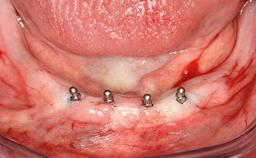

After flapless tooth extraction and a healing period of 6 weeks, a standard-diameter one-piece implant is placed. A gap between the implant and the facial bone wall is filled with autogenous bone chips harvested from the anterior nasal spine and covered with DBBM particles. Contour augmentation on the facial aspect is achieved using DBBM particles and a collagen membrane, according to the principles of guided bone regeneration (GBR). The flap is coronally repositioned for semisubmerged healing.